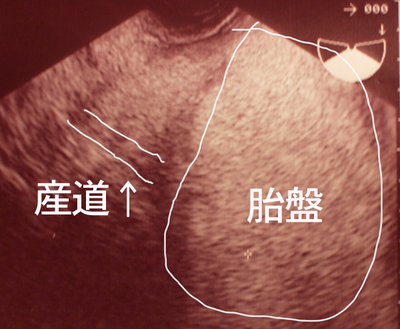

↓これが、奇跡の4日後に

胎盤じゃなくて産道の先に子供が見えるエコー!

ちなみに、今日みたのは

上のエコーと同じ位置に産道が見えて

胎盤でもやーっとしてるところにちゃんとお尻がみえました。